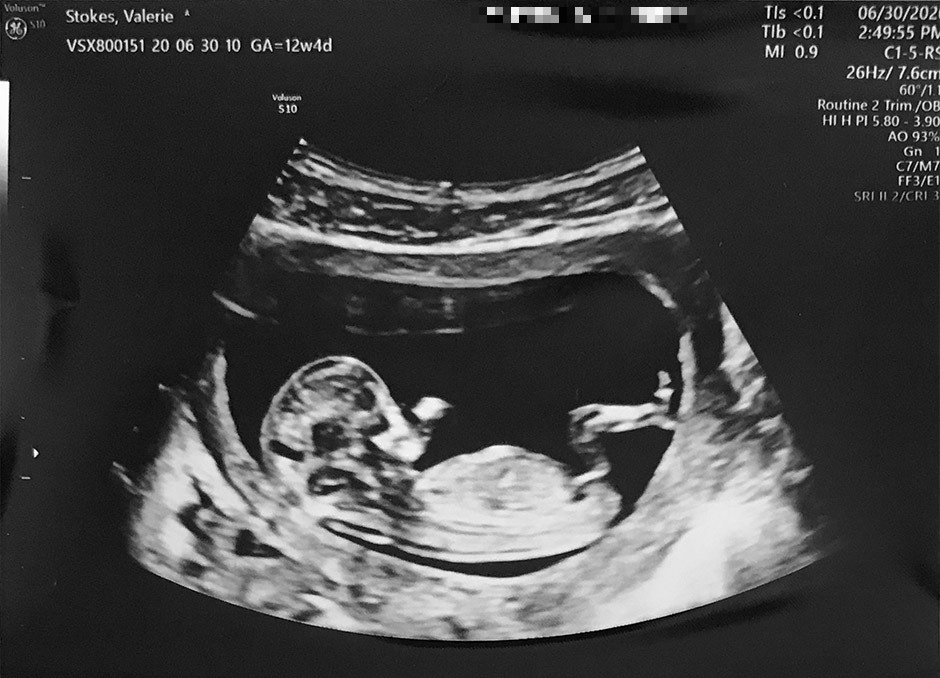

Sonogram

After trying for a few short months, the news came out on May 4, 2020 that Valerie was pregnant! They kept it a secret until after the first trimester ended and then finally broke the news to friends & family in August.